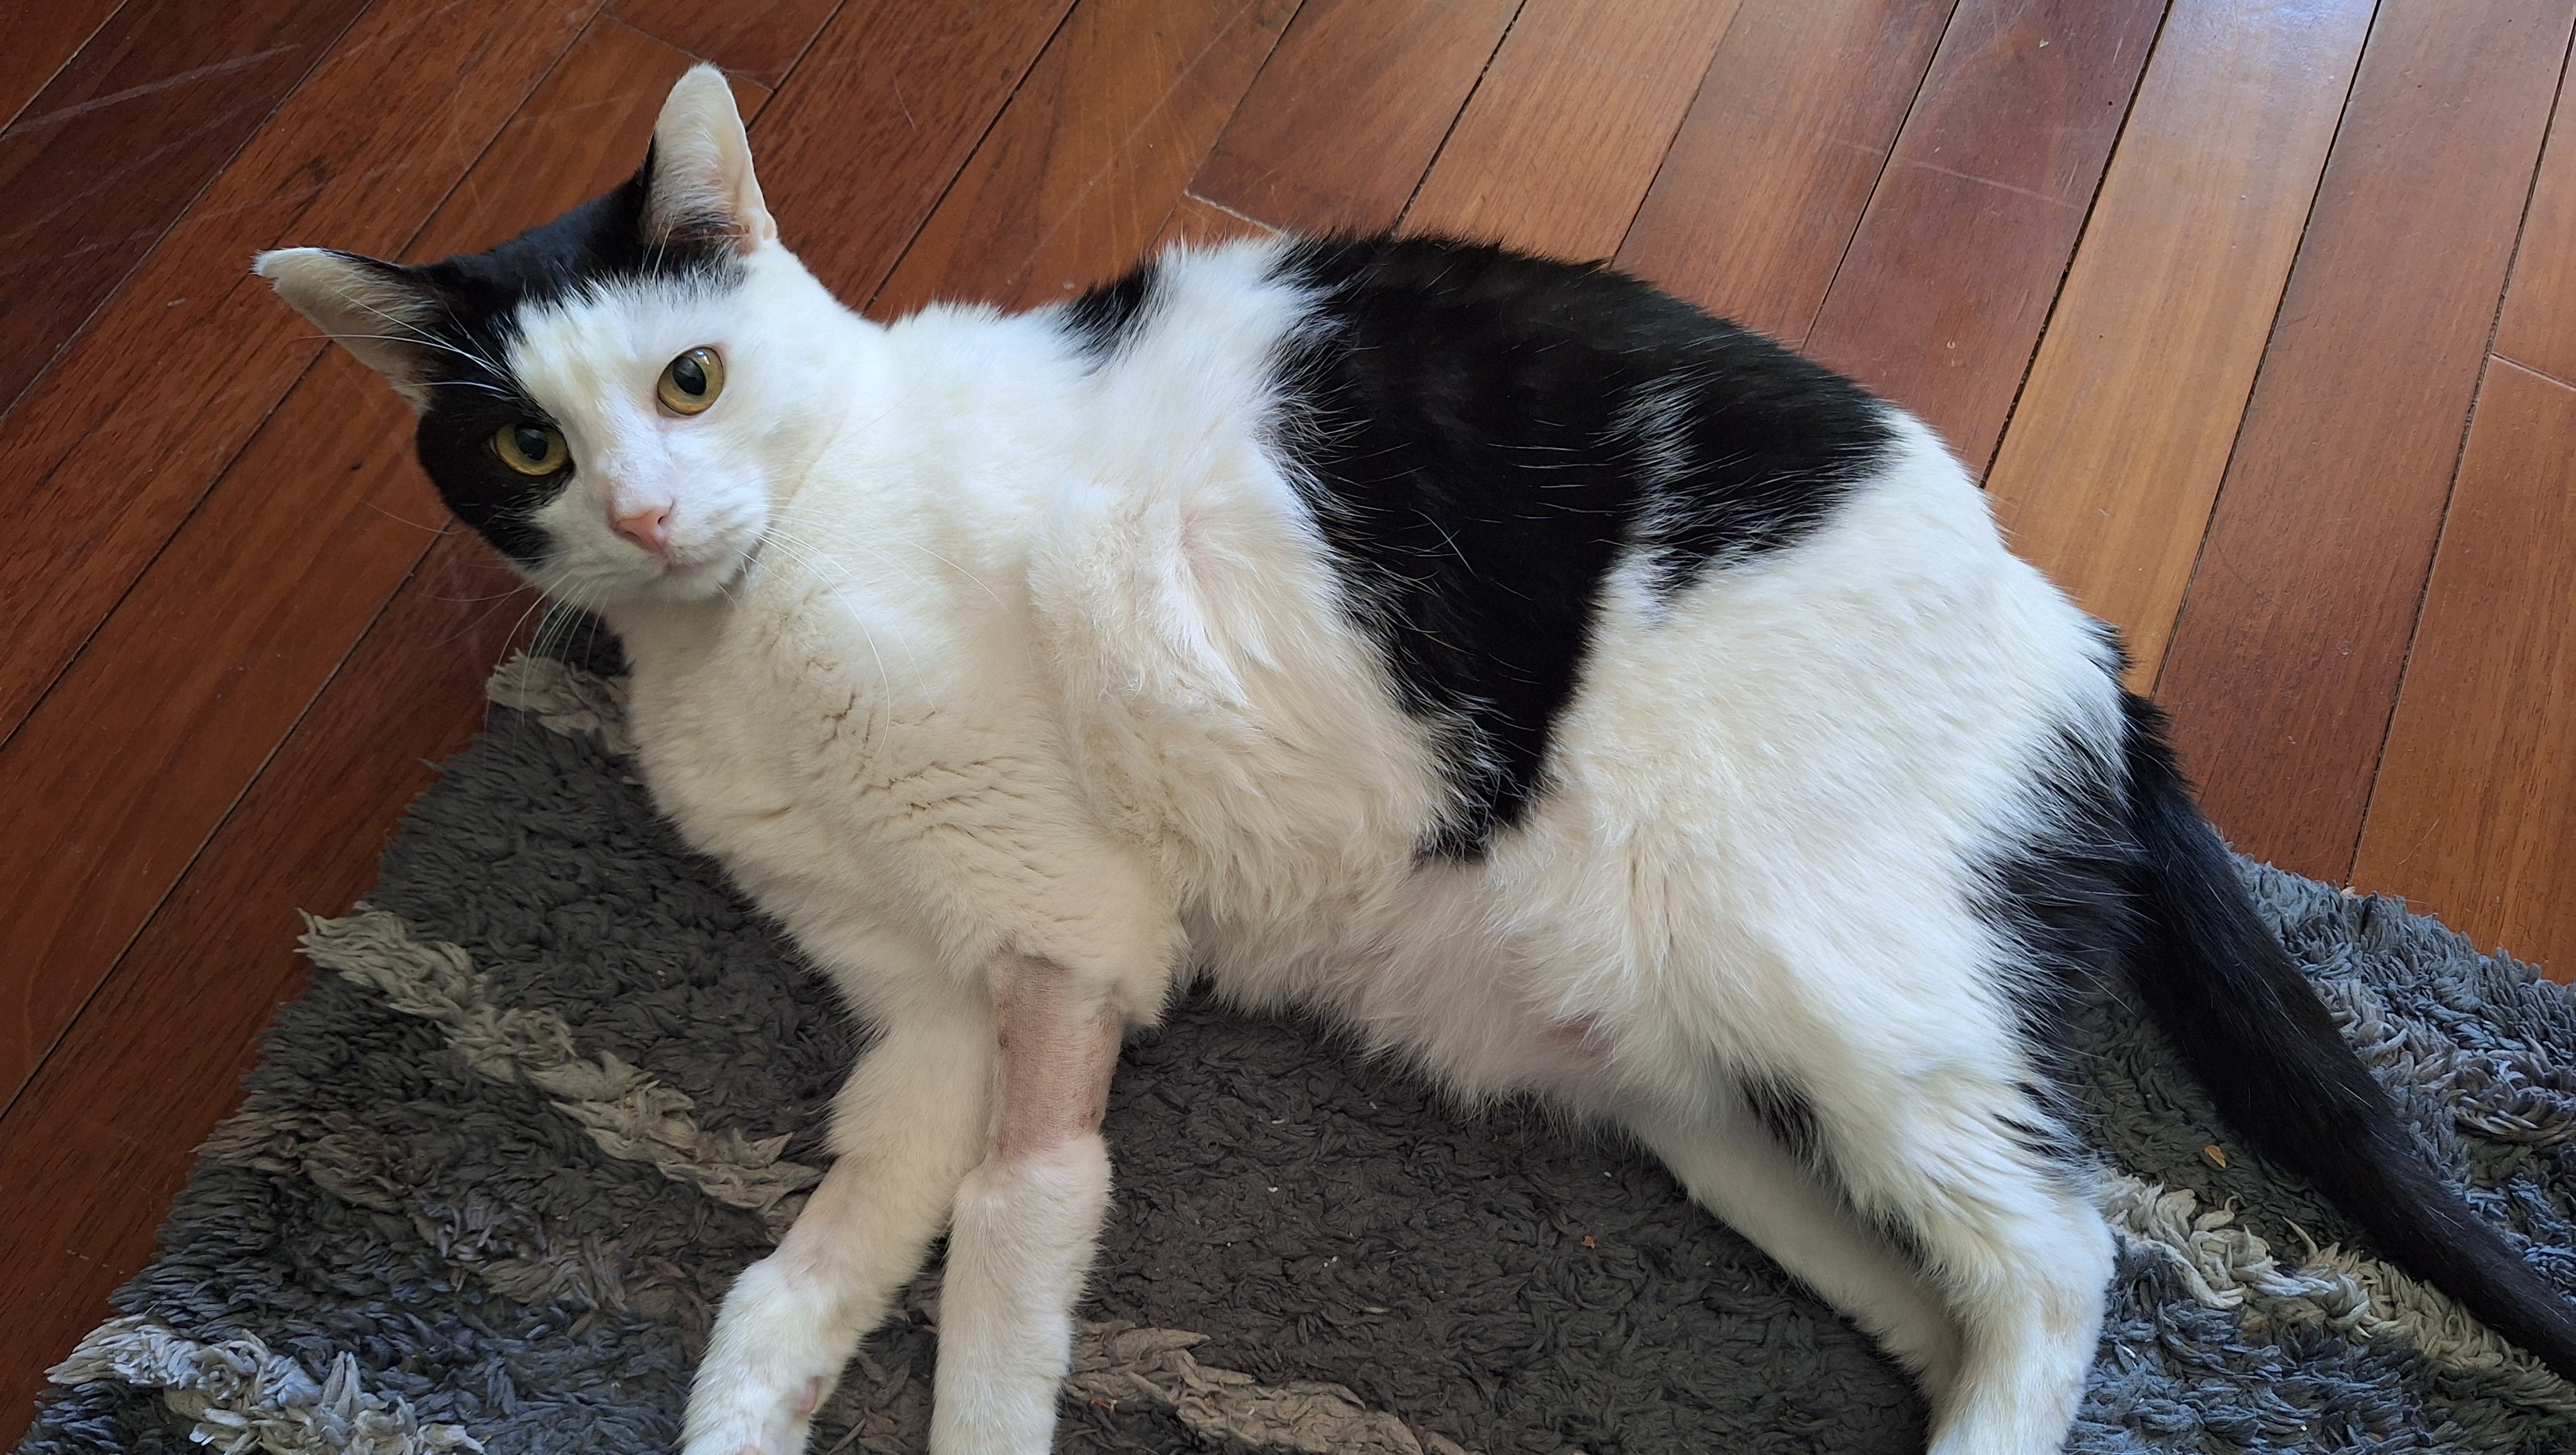

In late May of 2025 our cat, Badger, started walking oddly, acting like it was hard for him to coordinate his rear legs. After a few trips to our local vet to rule out the likely causes (nothing on xrays, blood work and kidneys were fine), we opted to take him to a Veterinary Teaching Hospital 3 hours away to see a neurologist. They suggested a MRI for further diagnosis. This procedure showed a small isolated mass on his spinal cord. Their team initially diagnosed it as a meningioma (non-cancerous tumor). To fully determine what it was the next option was surgery to remove the mass and get a biopsy. That went well (you can see the surgical incision in the main photo) however the surgeon said the mass was not on the cord, but in the cord, meaning it was much more likely to be cancerous. We braced for the worst, however based on the biopsy we learned that it was indeed a meningioma (although a very odd one). The image below of the MRI showing the location of the tumor on his 13th thoracic vertebrae.

Although Badger is doing well and recovering from surgery, the only way we can now treat the tumor is for him to undergo radiation therapy. Without it he'll slowly get worse, losing all motor function in the rear legs and eventually his organs (he'd have a few months before symptoms get worse). The prognosis with radiation is hard to known (given how rare these cases are) but if it's consistent with similar tumors in the brain it should give us several years of high quality time together where he will likely fully recover. He is an otherwise healthy member of our family!

We've decided to pursue the radiation as 1) we of course want to do the best for him and keep him around for as long as possible, and 2) we want to be able to add to the small data set of treatment and survival outcomes on this very rare tumor. As a scientist I know that data are always in limited supply. So we'd like to have Badgers' treatment serve to assist other pets and pet owners in the future be able to use his case to make more informed decisions. I've spoken to the Vet team at the teaching hospital and they are interested in publishing on this case as well!